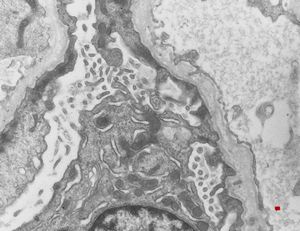

F,14y. | Alport syndrome - split and laminated, thick/thin basement membranes